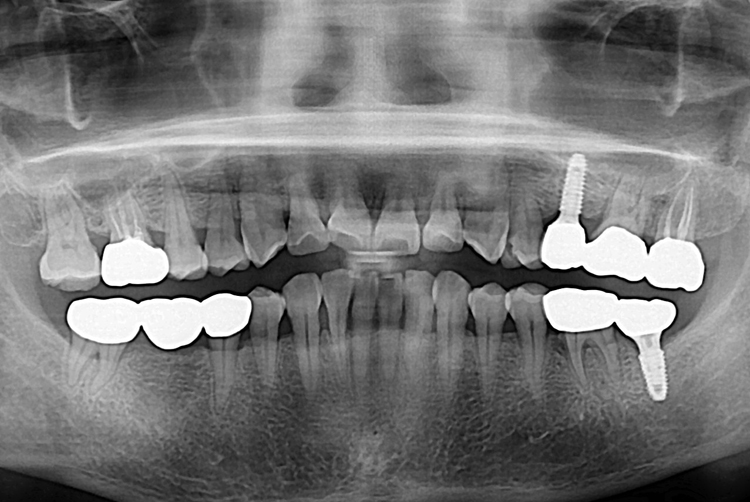

[임플란트] 어금니 임플란트

치료전 : 2018-08-21

세종치과는 많은 환자와 다양한 케이스를 바탕으로

항상 편안한 임플란트 수술을 제공하고자 노력하고,

오래동안 튼튼히 쓸 수 있는 임플란트 수술을 가장 큰 목표로 삼고 있습니다.